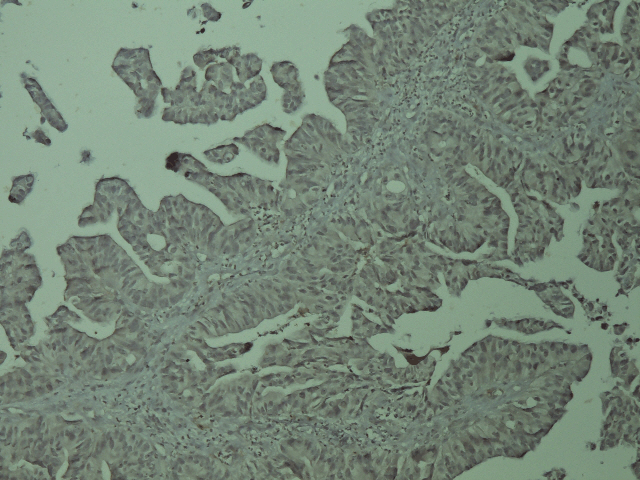

A 46-year-old man presented to us with complaints of swelling and pain in the lower gingiva. Examination of the oral cavity revealed a deep red and hemorrhagic mass that extend from tooth 27 to tooth 32 (figure 1). Medical history was remarkable for rectal adenocarcinoma for which he had undergone abdominoperineal resection one year earlier (T3N1M0), without any adjuvant treatment. The serum CEA and CA19-9 levels were 44 IU/ml and 19 IU/ml, respectively. A head-neck CT scan showed a 3.6 x 1.5 cm soft tissue mass on the right mandible with involvement of the underlying bone. Pathological examination by biopsy of the gingival tumor revealed moderately differentiated adenocarcinoma. Immunohistochemical (IHC) staining showed negativity for cytokeratin 7 and positivity for cytokeratin 20 (figures 2, 3). The gingival lesion was considered as the metastasis from the rectal cancer. A complete workup revealed liver and lung metastases.

Figure 2: Immunohistochemical staining negative for cytokeratin 7.